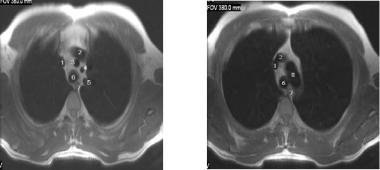

Рис. 12. Оценка ответа на химиотерапию лимфомы. Скан А показывает интенсивность накопления активности перед терапией: множественные метастазы в средостение, надключичные лимфоузлы, селезёнку и левый бронх. После 5 месячной химиотерапии (снимок В) наблюдается полная ремиссия заболевания.